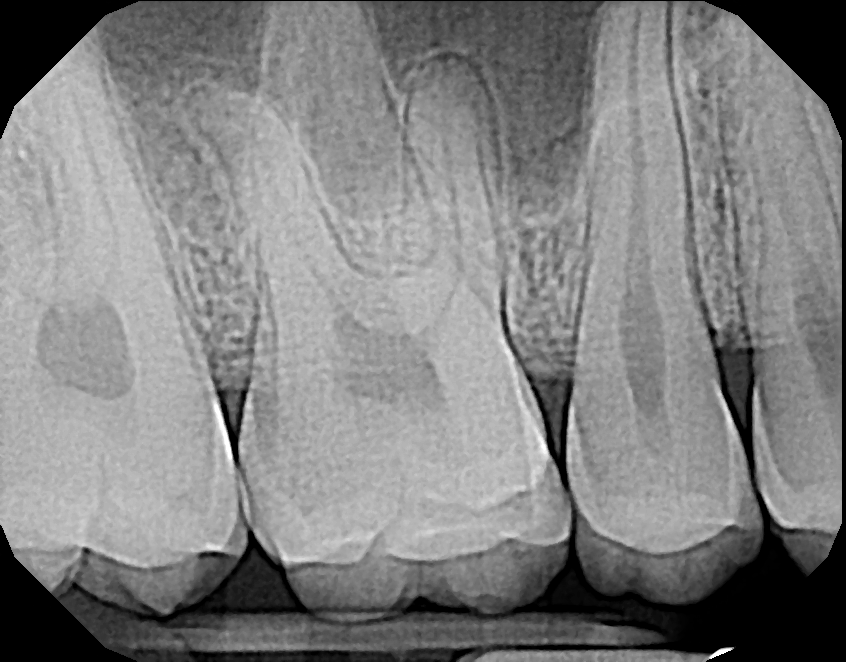

Image Quality

Ultimately, quality is the most important factor in a dental X-ray sensor. A sharp image ensures a proper diagnosis for patients. The Dream Sensor produces easy-to-view, crisp images that work with almost any existing dental software. The results of the direct comparison of DentiMax vs. Dexis are clear.

![]() X-ray taken with the DentiMax sensor shown in Sidexis 4™ software | ![]() X-ray taken with the Dexis™ sensor |